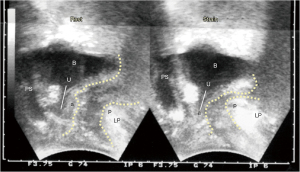

El ángulo anorrectal "A" (Figura 8) se forma por la contracción equilibrada hacia atrás/abajo del LP/MLA contra la contracción hacia adelante de (principalmente) el MPR. La laxitud del LUS debilitará las fuerzas del LP/MLA que se contraen contra el LUS. En términos relativos, el MPR se contrae con más fuerza que el LP/MLA; en consecuencia, el sistema muscular direccional (Figura 8, 3 flechas grandes) se desequilibra y el MPR hunde la pared rectal posterior, dando la impresión de una "contracción paradójica" o "espasmo" del MPR, como se observa en los proctogramas de defecación y los exámenes de ultrasonido (Figura 9). La Figura 10 demuestra cómo la reparación del LPU y el LUS restauró la anatomía tanto en reposo como con esfuerzo, y también restauró la funcióN (ver informe de caso a continuación).

Pérdida del equilibrio muscular pélvico monitoreada por ultrasonido tratada mediante la reparación del LPU y el LUS

Estudio experimental nº 6: reutilizado de (11). Copyright 2008, con permiso de Pelviperineology.

La paciente, de 49 años, paridad 3, presentó prolapso de segundo grado, dificultad para defecar, FI, IUE, nicturia y dolor pélvico crónico (1). El proctograma de defecación preoperatorio mostró un ángulo anorrectal agudo similar al de la ecografía preoperatoria (Figura 9). No hubo rectocele ni intususcepción rectal. Las reparaciones con cabestrillo LPU y LUS mejoraron sustancialmente los síntomas de vejiga e intestino; también se restableció la apariencia de la anatomía normal al hacer esfuerzo en la ecografía transperineal (Figura 10) que se atribuyó a la restauración del equilibrio de las cuatro fuerzas direccionales de la Figura 8. Con referencia a la Figura 9, la hendidura de la pared posterior del recto, tanto en reposo como al hacer esfuerzo, es consistente con la incapacidad del LP/MLA para equilibrar la contracción hacia adelante del MPR en la Figura 8. Al comparar la Figura 9 con la Figura 10, luego de la reparación LUS (nuevamente con referencia a la Figura 8), el LP/MLA ahora podía estirar el recto hacia atrás y hacia abajo contra el LUS, en un movimiento giratorio, para cerrar el ángulo anorrectal. Al mismo tiempo, el MPR se contrae hacia adelante para proporcionar un punto firme para la rotación del recto, y el MPC se contrae hacia adelante para estabilizar la pared anterior del ano. Un LUS firme requiere que el LP/MLA ejerza una fuerza contráctil máxima y un LPU firme para el MPC. El MPR se contrae directamente contra la sínfisis, por lo que su fuerza contráctil no se ve afectada por ningún daño en los ligamentos.